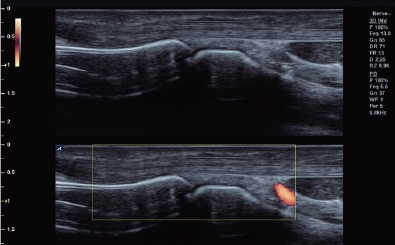

Finger in Power Doppler mode